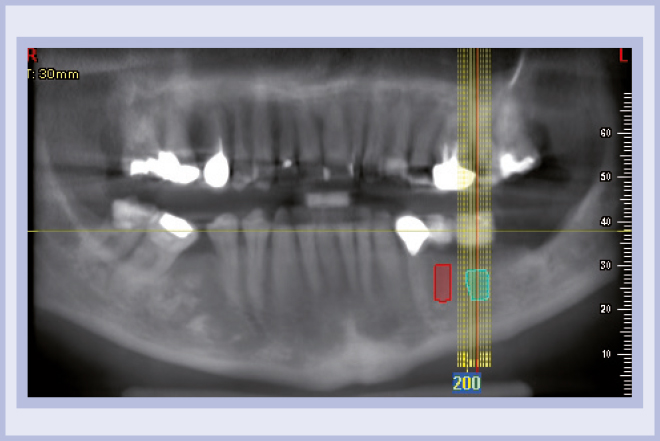

Per riabilitare la masticazione del terzo quadrante, con osso gravemente atrofico, si procede allo studio del caso con esame radiologico 3D e posizionamento virtuale di impianti Exacone® Leone. La prima valutazione è stata eseguita con il software dell’apparecchio radiografico Cone Beam presente in studio. Dopo aver verificato che la quantità di osso residuo fosse sufficiente all’inserimento di due impianti, seppur di dimensioni ridotte, in sede 3.5 e 3.6 senza l’ausilio di tecniche di rigenerazione ossea (Figg. 1-3), si richiede al laboratorio di confezionare una mascherina radiologica con ceratura diagnostica radiopaca e repere standardizzato a livello incisale come da protocollo Leone (Figg. 4, 5). Si verifica quindi clinicamente l’assenza di mobilità della mascherina dopo il posizionamento nel cavo orale del paziente (Figg. 6, 7). Si effettua una CBCT con la mascherina in posizione e l’esame viene inviato in formato DICOM all’azienda Leone assieme al modello master della paziente. L’azienda provvede quindi ad inviare agli Autori il software 3Diagnosys (software di progettazione) in licenza monopaziente con caricati i file DICOM ricevuti; il software viene quindi utilizzato per la progettazione definitiva del caso (Figg. 8-12).

- Figg. 1-3 – Esame Cone Beam iniziale, si verifica la fattibilità di inserimento impianti

- Fig. 2 mento impianti

- Fig. 3